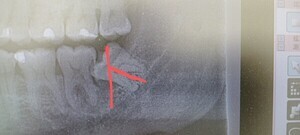

少し見えて横になった親知らず

親知らずのレントゲン

親知らずの歯はどこの場所?

親知らずは、永久歯(大人の歯)の中で最後に発育する歯で、中切歯(最前方の前歯)から数えて8番目の最後方歯に位置しています。

18歳前後から生えてくるので、20代前半までに抜歯するのがおすすめです。

親知らずは必ずしも抜かなければいけないものではありませんが、痛みや腫れを繰り返す場合や、他の歯に影響を及ぼしてしまう可能性がある場合は抜歯を行う必要があります。

親知らずが腫れる理由は?

親知らずの半分が歯ぐきの中に埋まっていたり、傾いていたりするので、親知らずの周りの歯ぐきの“くぼみ”に歯垢(プラーク、細菌)が溜まりやすく不潔となり、体調を崩し免疫力が落ちると、そこから炎症を起こし、周辺の歯ぐきが腫れてきます。

親知らずを原因とする歯周炎は「智歯周囲炎」と呼ばれ、通常のむし歯による歯周炎に比べ、炎症の程度が強いのが特徴です。このため、痛みがひどく、頬まで腫れた、口が開きにくいといった重い症状を引き起こしやすくなります。